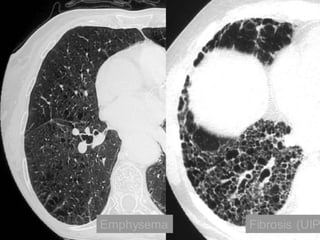

Fibrosis and Emphysema

CT findings:

• Relatively well-defined, low attenuation areas

with very thin (invisible) walls, surrounded by

normal lung parenchyma.

• As disease progresses:

– Amount of intervening normal lung decreases.

– Number and size of the pulmonary vessels

decrease.

– +/- Abnormal vessel branching angles (>90o), with

vessel bowing around the bullae.